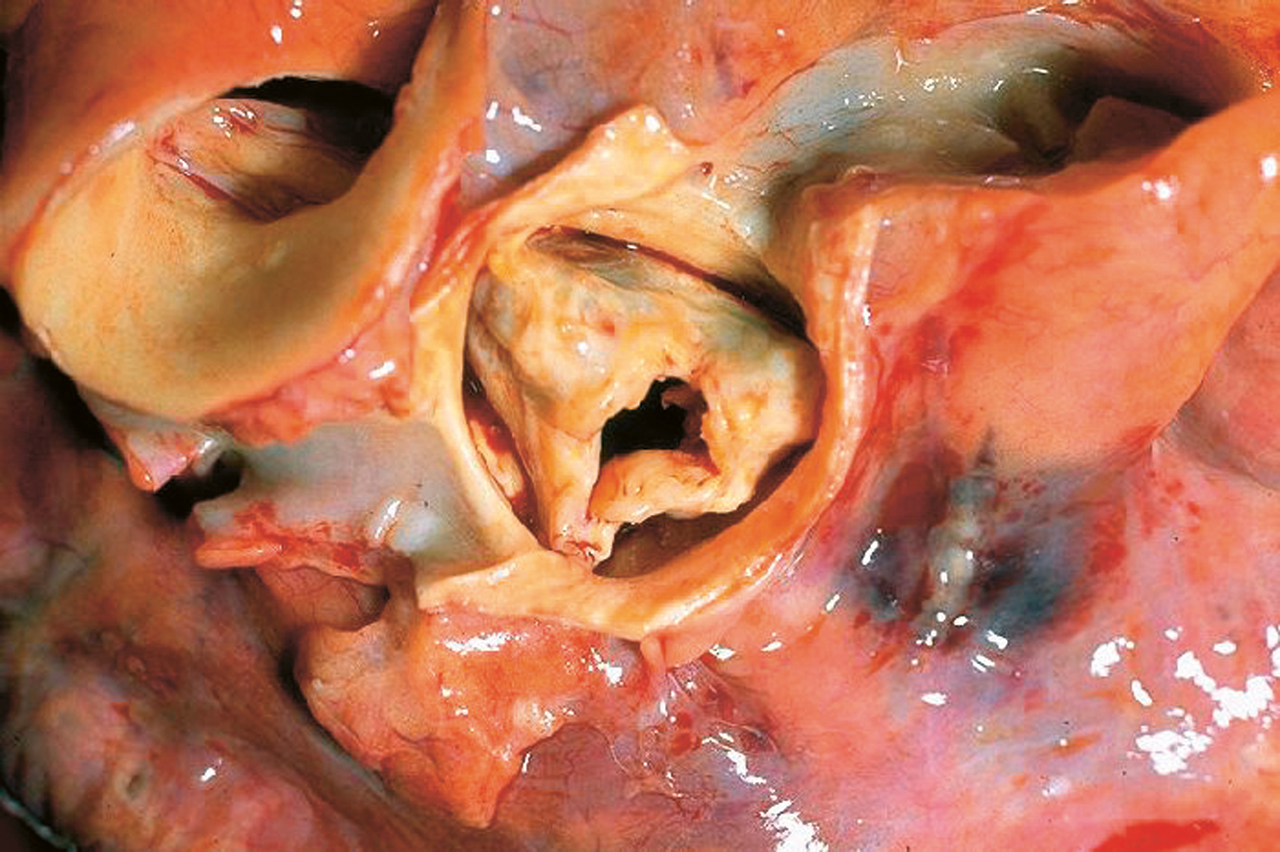

3,4 % der über 75-Jährigen haben eine schwere Aortenklappenstenose. Jeder Zweite stirbt innerhalb eines Jahres daran. 3,4 % der über 75-Jährigen haben eine schwere Aortenklappenstenose. Jeder Zweite stirbt innerhalb eines Jahres daran. © wikipedia/CDC, Dr. Edwin P. Ewing, Jr

schwere Aortenklappenstenose schwere Aortenklappenstenose © wikipedia/CDC, Dr. Edwin P. Ewing, Jr